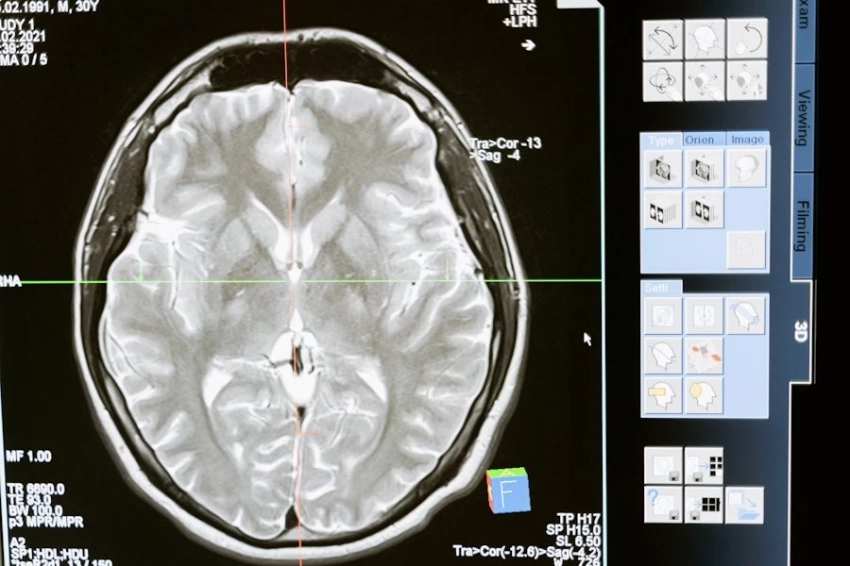

Искусственный интеллект расшифровывает пути интеллекта мозга

Фото из открытых источников В новом исследовании, опубликованном в PNAS Nexus, ученые продемонстрировали, что искусственный интеллект может предсказывать различные типы человеческого интеллекта, анализируя связи в мозге. Используя данные нейровизуализации сотен здоровых взрослых, они обнаружили, что прогнозы...